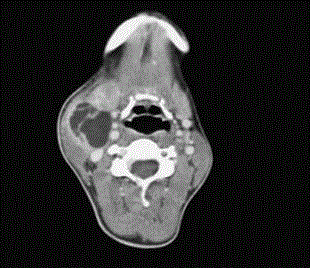

zystische Raumforderung am Hals rechts , axiale Schichtung CT.

V.a Laterale Halszyste